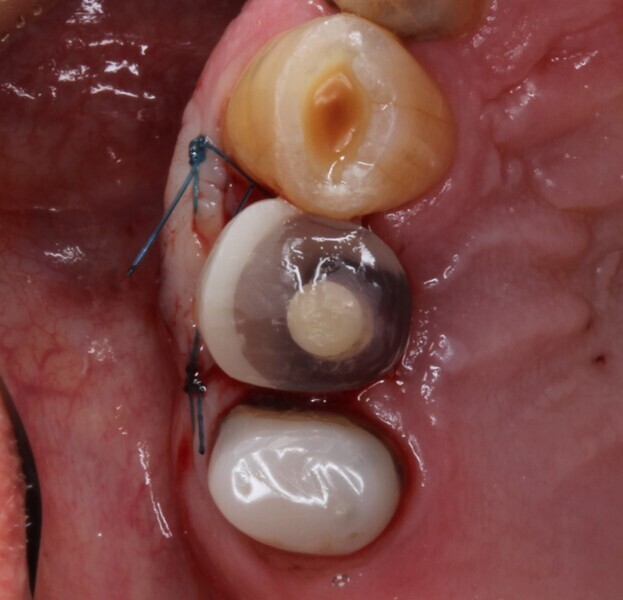

A male patient presented in our dental office with a severely broken maxillary right first premolar (tooth #14) that had been designated for extraction a number of years before. The tooth immediately distal (tooth #15) was also in need of substantial dental treatment (Figs. 1 & 2). The patient had hypertension that was controlled with anti-hypertensive medication, but was otherwise medically fit. He intended to have the colour of his anterior teeth improved, but wished to address the issues on his maxillary right side first.

Tooth #14 was deemed unrestorable, and so it was decided to extract the tooth (Figs. 3 & 4), wait for bony healing and replace it with an implant with a provisional restoration. During the healing process, endodontic therapy would be performed on tooth #15. After bony integration, implant #14 would be restored with a screw-retained direct-to-implant zirconia crown, and tooth #15 would also be restored with a complete zirconia crown. A deliberately lighter shade would be chosen, factoring in the patient’s long-term desire to improve the colour of his teeth.

Fig. 2: Pre-op situation, showing the maxillary right first premolar with a poor restorative prognosis.